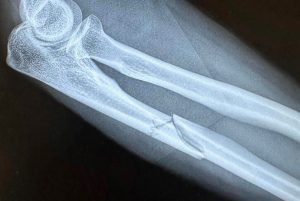

ALCANTARILLA (Murcia). Viernes 17 de abril de 2026 – NdP – El torero José María Trigueros ha sido intervenido quirúrgicamente con éxito para la retirada del material de osteosíntesis —placa de titanio y 8 tornillos— que le fueron implantados tras el grave percance sufrido la pasada temporada.

La cirugía, llevada a cabo por el doctor Francisco Martínez en el Hospital Viamed San José de Alcantarilla (Murcia), se ha desarrollado según lo previsto y con resultado plenamente satisfactorio, tal y como han confirmado los servicios médicos tras la intervención. El cúbito presenta una consolidación ósea óptima, lo que ha permitido proceder a la retirada del material sin complicaciones.

Martes 14 de abril de 2026 – – NdP – El matador de toros murciano José María Trigueros tendrá que someterse nuevamente a una intervención quirúrgica en su brazo derecho, con el objetivo de retirar la placa de titanio y los ocho tornillos que le fueron implantados para fijar el cúbito tras el grave percance sufrido a comienzos de la pasada temporada.

La lesión se produjo cuando el diestro fue cogido por un toro de salida al recibirlo de rodillas con una larga cambiada, resultando fracturado el citado hueso del antebrazo. El material de osteosíntesis implantado cumplió correctamente su función durante el proceso de consolidación ósea, si bien, por una posible presión muscular u otras circunstancias, está provocando en la actualidad molestias y debilidad en el brazo, que persisten a pesar del intenso trabajo de recuperación realizado en este tiempo.

Con el fin de poner punto final a este proceso y erradicar definitivamente los dolores, el torero será intervenido por segunda vez por el prestigioso doctor Francisco Martínez, quien procederá a la retirada de la placa y los tornillos. Hace un tiempo se le practicó un TAC en la extremidad afectada para confirmar que el cúbito se encuentra totalmente soldado y presenta una densidad ósea óptima, condiciones necesarias para abordar la intervención con plenas garantías.